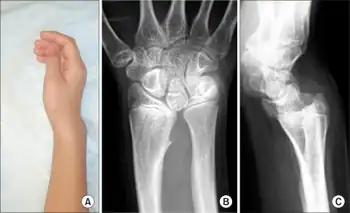

| Madelung deformation, a type of bone malformation associated with both SHOX and SHOXY genes mutations. | |

Madelung's deformity is usually characterized by malformed wrists and wrist bones and is often associated with Léri-Weill dyschondrosteosis. It can be bilateral (in both wrists) or just in the one wrist. It has only been recognized within the past hundred years. Named after Otto Wilhelm Madelung (1846–1926), a German surgeon, who described it in detail, it was noted by others. Guillaume Dupuytren mentioned it in 1834, Auguste Nélaton in 1847, and Joseph-François Malgaigne in 1855.

It is a congenital subluxation or dislocation of the ulna's distal end, due to malformation of the bones. Sometimes, minor abnormalities of other bone structures, often caused by disease or injury, such as a fracture of the distal end of the radius with upward displacement of the distal fragment. The deformity varies in degree from a slight protrusion of the lower end of the ulna, to complete dislocation of the inferior radio-ulnar joint with marked ulnar deviation of the hand. Severe deformities are associated with congenital absence or hypoplasia of the radius.

The male:female rate of this disorder is 1:4. The incidence is unknown, and there is no described racial predominance. Even though Madelung's Deformity is considered a congenital disorder, symptoms sometimes aren't seen until adulthood. In most cases, symptoms find their onset during midchildhood. At this age, the relatively slower growth of the ulnar and palmar part of the radius, leads to an increasingly progressive deformity. Pain and deformity are the main symptoms patients present with.[1] Typical clinical presentation consists of a short forearm, anterior-ulnar bow of the radius and a forward subluxation of the hand on the forearm. As mentioned before, the severity of the disorder varies greatly, which also leads to a spectrum of presentation.

Madelung deformity of the wrist is caused by a growth disturbance in the inferior volar part of the epiphysial growth plate in the distal radius, resulting in a volar placed slope of the lunate facet and scaphoid facet. This produces volar translation of the hand and wrist. The ulna continues growing straight, resulting in a dorsally prominent distal ulna. It occurs predominantly in adolescent females, who present with pain, decreased range of motion, and deformity. It often has a genetic cause and is associated with mesomelic dwarfism and a mutation on the X chromosome. Attempts can be made to treat the deformity surgically by addressing the deforming bone and fibrous bands called "Vickers ligament". This is an abnormal ligament formed between the Lunate bone of the wrist and the radius and is found in 91% of cases of Madelung's deformity.

Diagnosis is normally confirmed by X-rays.